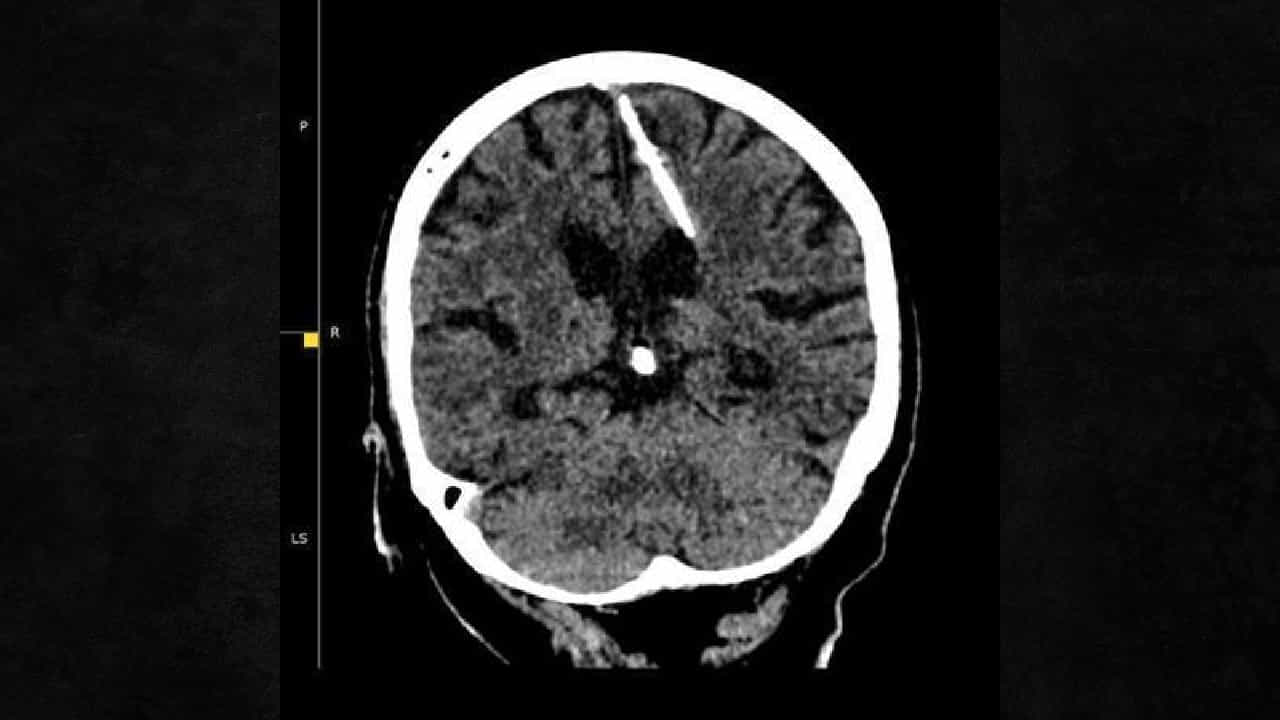

मॉस्को | 5 ऑक्टोबर 2003 : एका 80 वर्षीय रशियन वृद्धेच्या डोक्यात सुई असल्याचे डॉक्टरांच्या तपासात उघड झाले आहे. ही सुई तिच्या डोक्यात कशी काय गेली याचा धक्कादायक तर्क काढण्यात आला आहे. आरोग्य मंत्रालयाने टेलिग्राम पोस्टवर लिहीले आहे की या महिलेचा एक्स रे काढला असता डोक्यात तीन सेंटीमीटरची सुई आढळली. डॉक्टरांना नेमकं केव्हा हे कळलं हे स्पष्ट लिहीले नसले तरी साल 2023 मध्ये ही धक्कादायक घटना आहे. या घटनेमागे या वृद्धेला तिच्या आई-वडीलांनी ती लहान असताना सुई टोचून मारण्याचा प्रयत्न केला असावा असे म्हटले जात आहे.

रशियन मंत्रालयाने महिलेचे नाव सांगितलेले नाही. डॉक्टरांनी म्हटले आहे की तिच्या लहानपणी तिच्या आई-वडीलांनी तिला मारण्याचा प्रयत्न केला असावा असे म्हटले आहे. युद्ध काळात नैराश्याने ग्रासलेले आई-वडील नवजात शिशूच्या डोक्यात नरम हाडांमध्ये सुई टोचायचे. हाडे विकसित झाली नसल्याने सुई आत जाते. दुष्काळातही अशा घटना असामान्य मानल्या जात नव्हत्या.

या बुजुर्ग महिलेचा जन्म साल 1943 च्या दरम्यान झाला तेव्हा बालहत्येचे प्रमाण जास्त होते. आरोग्य मंत्रालयाने दिलेल्या माहीतीनूसार ही महिला आश्चर्यकारक वाचली आणि तिला त्या सुईमुळे कधी डोके दुखीचा सामनाही करावा लागला नसल्याने बाब उघड झाली नाही. आता डॉक्टरांनी सुई काढण्याचा प्रयत्न करणार नसल्याचे म्हटले आहे. कारण या वयात वृद्धेची सर्जरी केली तर तिची अवस्था आणखीन खराब होईल. त्यामुळे या वृद्धेला निरीक्षणाखाली ठेवण्यात येणार असल्याचे डॉक्टरांनी म्हटले आहे.